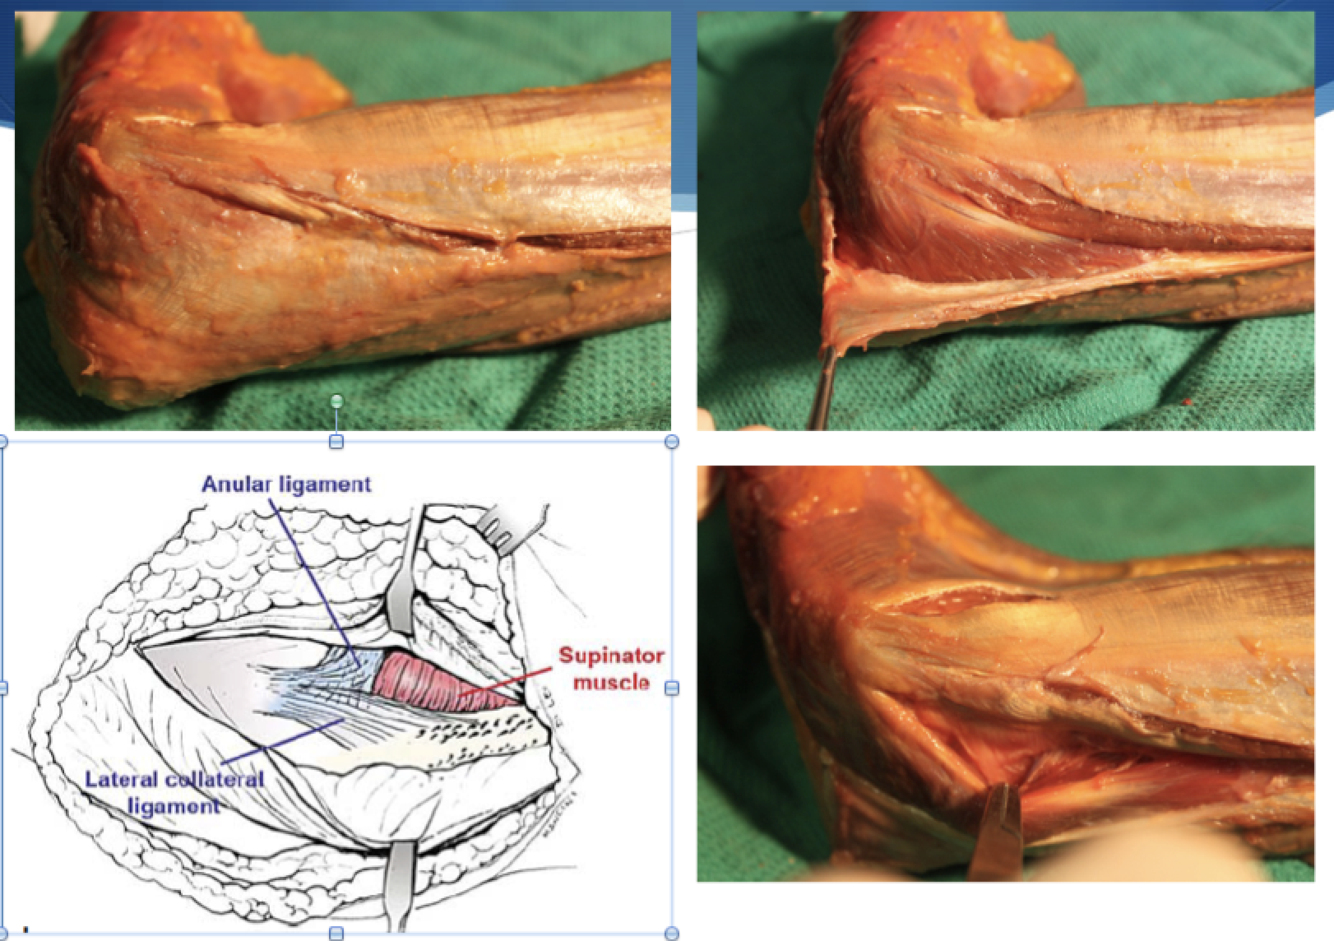

Kocher Approach

Interval: Anconeus (radial n.) & ECU (PIN)

Approach: Look for fat stripe between the two. Anconeus fibres will run obliquely. Will need to elevate some of supinator to reveal distal insertion of LUCL on crestor supinatore.

Dangers: PIN, LUCL

* can extend proximally by detatching anconeus from its origin on the distal humerus, and triceps from lateral intramuscular septum.

Kaplan

Interval: EDC (PIN), ECRL/ECRB (Radial N., PIN)

Approach: Split interval above. Proximal interval of the Thompson approach to the forearm.

Dangers: PIN

*pictured: kocher vs kaplan